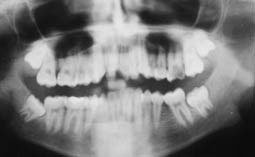

La radiographie panoramique montrait l’absence de la 36, une lésion pulpaire sur la 26 et la rétention de la 48 (Fig. 8).

L’examen radiologique confirme les résultats occlusaux et esthétiques (Fig. 21, 22).